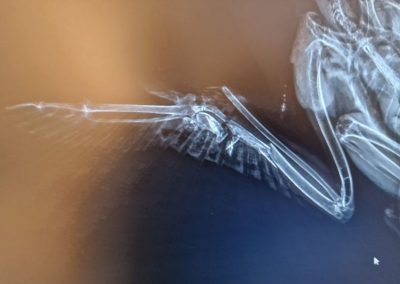

In unserer modernen, verbauten Welt ist der Luftraum kein sicherer Ort mehr. Was für uns Fortschritt und Infrastruktur bedeutet, wird für Eulen, Greif- und Wasservögel oft zur tödlichen Falle. Eine Wildvogelstation ist weit mehr als nur ein Ort für die Aufzucht flauschiger Küken – sie ist ein Lazarett an der vordersten Front.

Die Verletzungen, die wir täglich behandeln, sind keine Unfälle der Natur. Sie sind die direkten Folgen unseres menschlichen Wirkens:

• Infrastruktur-Opfer: Anflüge gegen Hochspannungsleitungen und die rotierenden Schaufeln von Windrädern sorgen für schwerste Traumata und Amputationen

• Tödliche Barrieren: Stacheldraht zerschneidet Schwingen; Glasfronten und der Straßenverkehr führen zu massiven inneren Verletzungen und Knochenbrüchen.

Die folgenden Bilder zeigen ungeschönt den Alltag in der medizinischen Notversorgung. Sie sehen Blut, offene Wunden und chirurgische Eingriffe. Das ist die notwendige, harte Arbeit hinter den Kulissen. Wir kämpfen um jedes Leben – mit Skalpell, Verband und fachmedizinischer Expertise –, um die Fehler wiedergutzumachen, die unsere Zivilisation verursacht hat.

Die folgenden Aufnahmen sind nichts für schwache Nerven. Sie zeigen Blut, offene Frakturen und den harten Kampf im Operationssaal. Wir zeigen sie bewusst. Denn diese Bilder sind die ungeschönte Antwort auf unsere Art zu leben.

Hinter jedem Foto steht ein Schicksal, ein Kampf und unser unermüdlicher Einsatz, das Unrecht der Zivilisation medizinisch zu korrigieren.